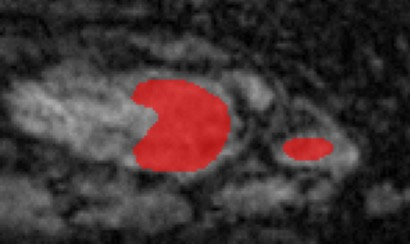

Medical data often exhibits long-tail distributions with heavy class imbalance, which naturally leads to difficulty in classifying the minority classes (i.e., boundary regions or rare objects). Recent work has significantly improved semi-supervised medical image segmentation in long-tailed scenarios by equipping them with unsupervised contrastive criteria. However, it remains unclear how well they will perform in the labeled portion of data where class distribution is also highly imbalanced. In this work, we present ACTION++, an improved contrastive learning framework with adaptive anatomical contrast for semi-supervised medical segmentation. Specifically, we propose an adaptive supervised contrastive loss, where we first compute the optimal locations of class centers uniformly distributed on the embedding space (i.e., off-line), and then perform online contrastive matching training by encouraging different class features to adaptively match these distinct and uniformly distributed class centers. Moreover, we argue that blindly adopting a constant temperature $\tau$ in the contrastive loss on long-tailed medical data is not optimal, and propose to use a dynamic $\tau$ via a simple cosine schedule to yield better separation between majority and minority classes. Empirically, we evaluate ACTION++ on ACDC and LA benchmarks and show that it achieves state-of-the-art across two semi-supervised settings. Theoretically, we analyze the performance of adaptive anatomical contrast and confirm its superiority in label efficiency.

翻译:医学数据经常呈现长尾分布和重度类别不平衡,这自然导致在对少数类别(即边界区域或罕见目标)进行分类时出现困难。最近的研究在长尾情况下通过装备医学影像的无监督对比标准,明显改进了半监督医学图像分割。然而,在标记的数据部分中,类别分布也极为不平衡,因此它们的表现如何仍不清楚。在本研究中,我们介绍一种采用自适应解剖对比度改进的对半监督医学分割行动的框架(ACTION++)。具体来说,我们提出了一种自适应监督对比损失,它首先在嵌入空间上计算出不同类别的优化位置(即离线),然后通过鼓励不同类别之间的特征与这些不同和均匀分布的类别中心相适应的在线对比匹配训练来进行自适应匹配。此外,我们认为,在长尾医疗数据中盲目采用常温度$\tau$不是最优的,因此通过一个简单的余弦计划来使用动态$\tau$来产生更好的多数类别和少数类别之间的分离。在实证方面,我们在ACDC和LA基准测试中评估ACTION++,并展示了其在两种半监督设置下的最新成果。从理论上讲,我们分析了自适应解剖对比度的性能,并证实了它在标签效率上的优越性。